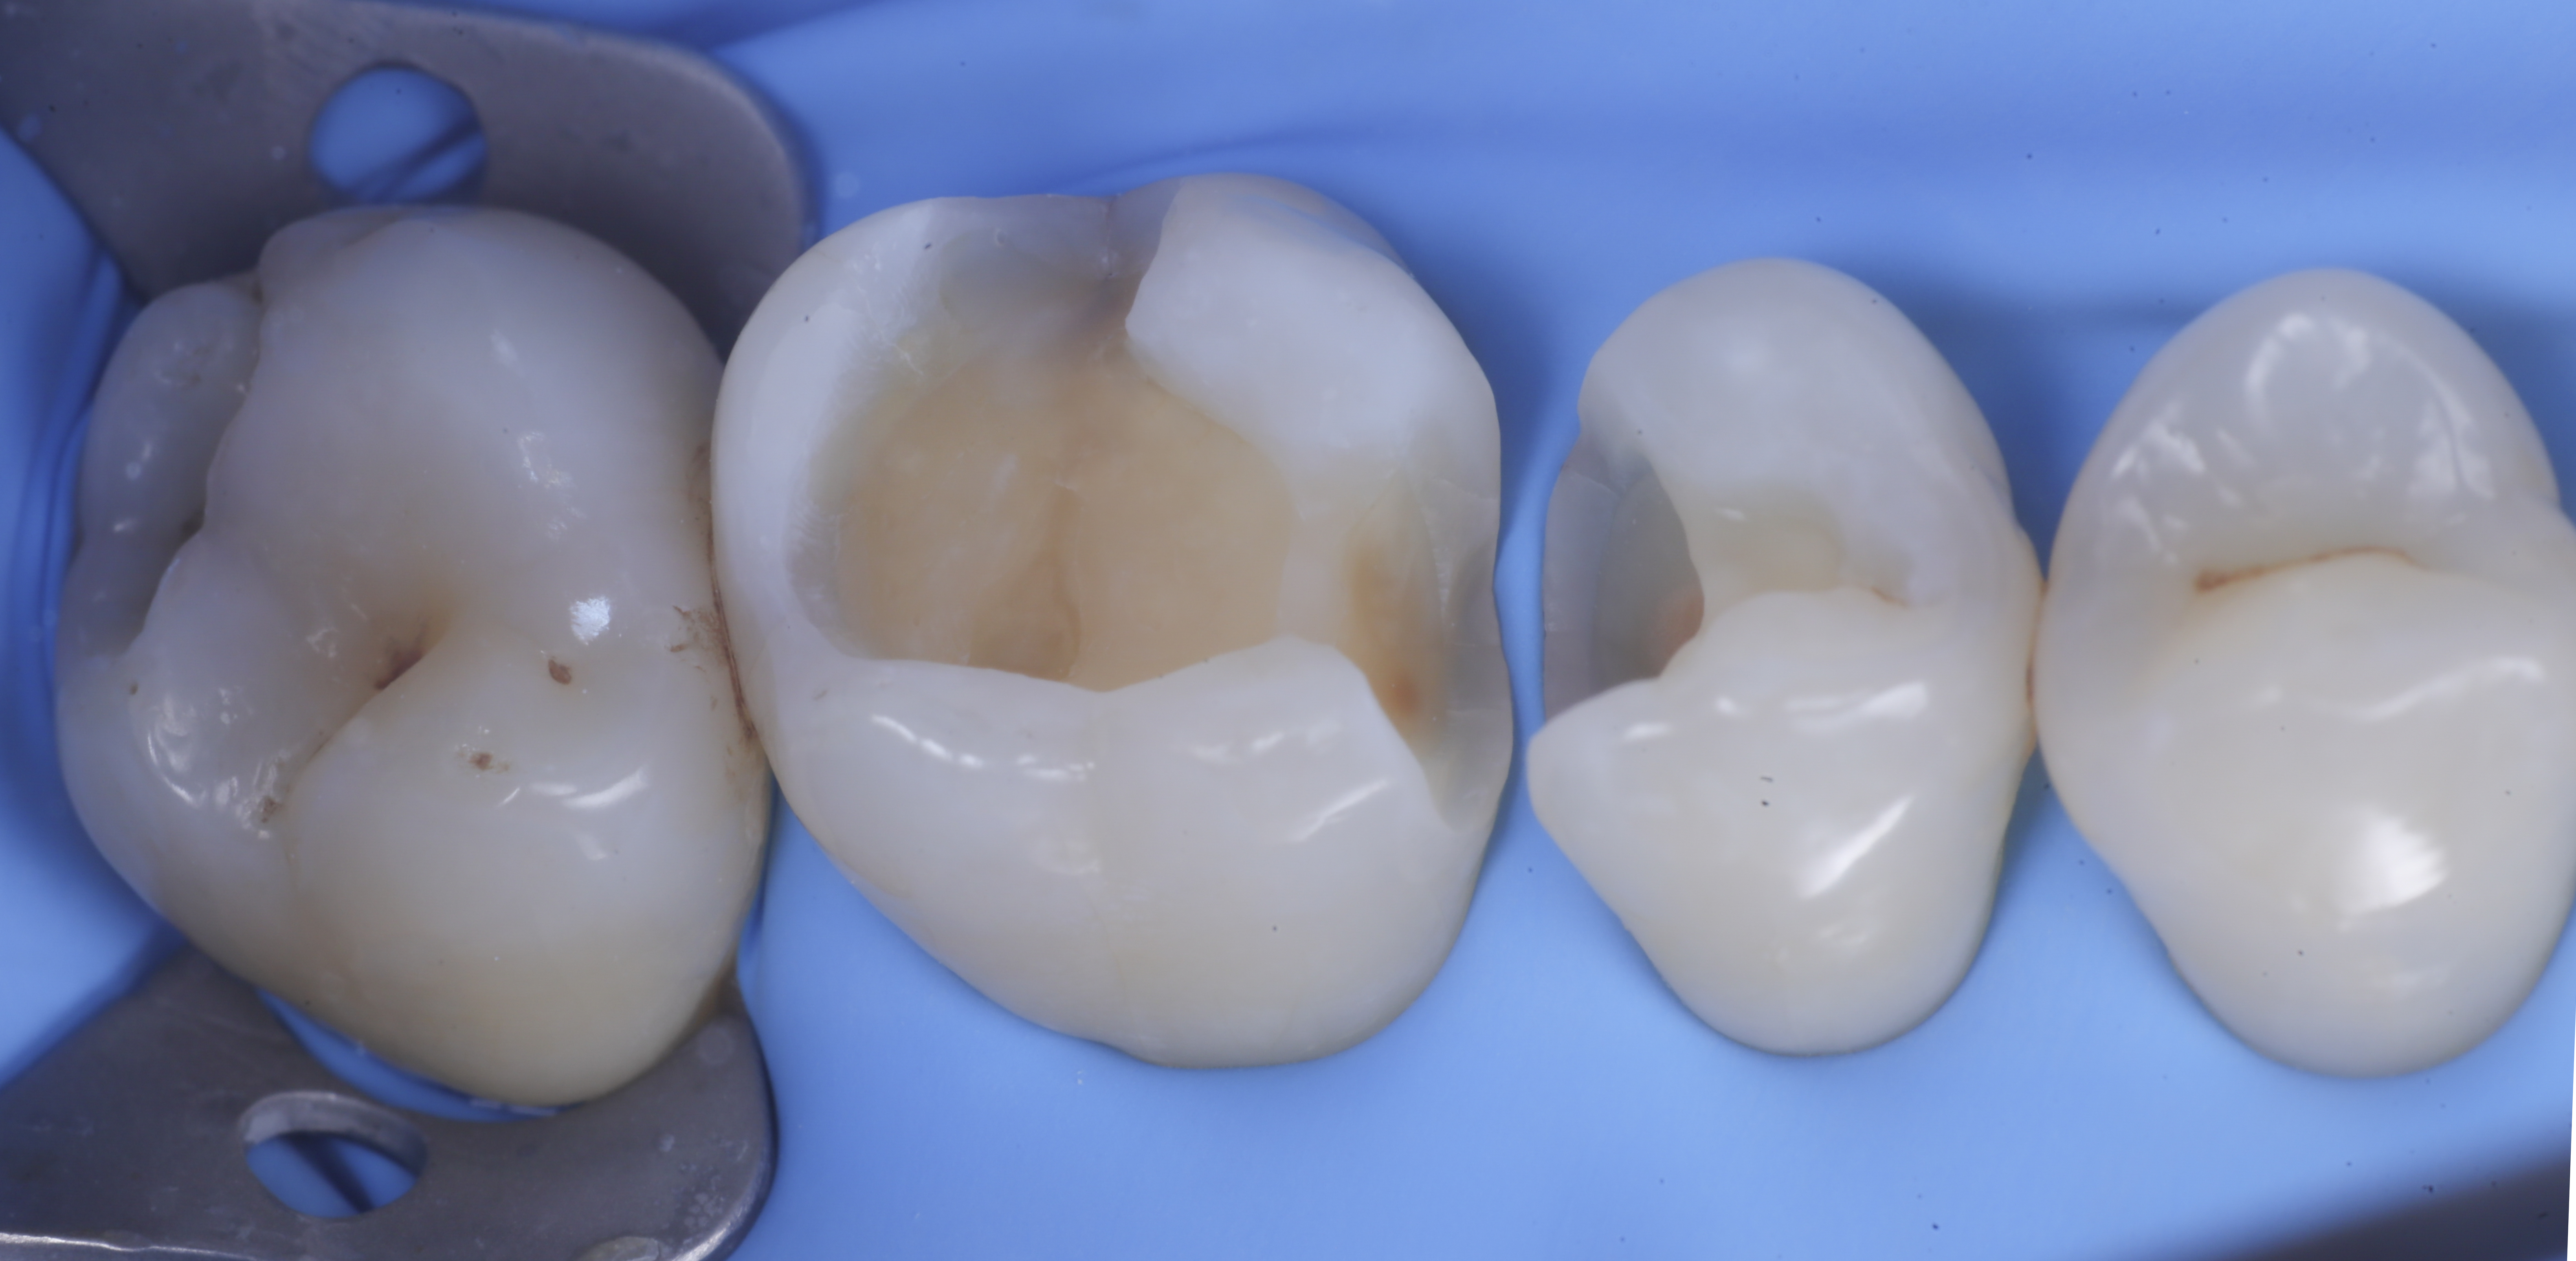

foto 2 Isolamento e aspetto delle cavità ultimate

foto 4 Aspetto della chiusura cervicale e sulle pareti assiali dato dalla prima matrice

foto 5 Aspetto della chiusura cervicale e sulle pareti assiali della seconda matrice

Una volta eliminato completamente il composito, si procede con la detersione della dentina con frese multilama ed alla rifinitura dei margini di smalto che dovranno essere robusti e puliti.

Dopo il posizionamento del cuneo, anello e delle due matrici sezionai, selezionate per altezza e raggio di curvatura, si procede con l’applicazione dell’adesivo universale, previa pre-mordenzatura dello smalto.